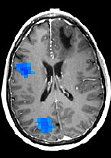

ischemic strokeResting-state network connectivity predicts recovery in ischemic Stroke.

The goal here is to examine cortical plasticity due to learning and experience in normal adult humans using ESI. We are specifically interested in cortical plasticity in response to dynamic stimuli in the time-scale of tens to hundreds of milliseconds. We have been examining plasticity, associated with perceptual learning, in representations of simple and complex acoustic stimuli as well as speech and language stimuli. We are also examining plasticity of somatosensory and motor representation changes due to training and perceptual learning.